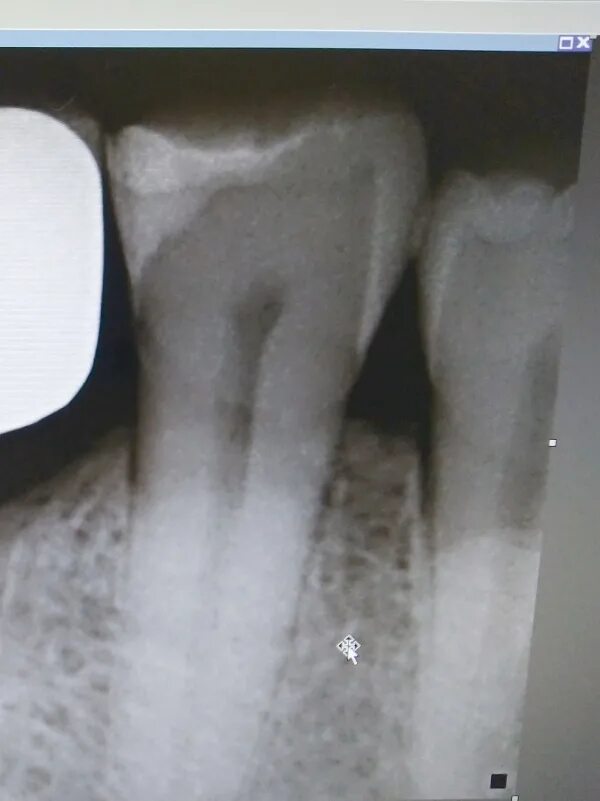

Зуб пульсирует и болит